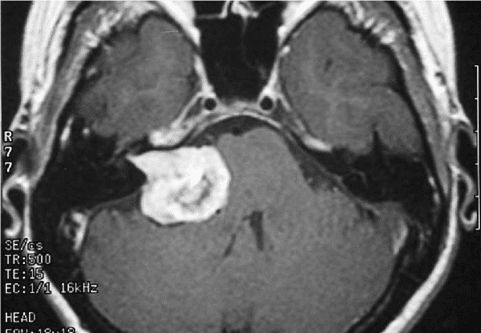

- КТ та МРТ для виявлення місця витоку.

- МРТ (магнітно-резонансна томографія) є додатковим методом для оцінки м’яких тканин та пошкоджень мозкових оболонок.

- Післяопераційна (ятрогенна) лікворея. Виникає в результаті хірургічних маніпуляцій, найчастіше на черепі або в області носових пазух. Частота цього виду ліквореї досягає 16% серед пацієнтів, які перенесли операції в краніобазальній області, таких як видалення пухлин. Особливо часто післяопераційна лікворея спостерігається після видалення новоутворень у зоні основи черепа.